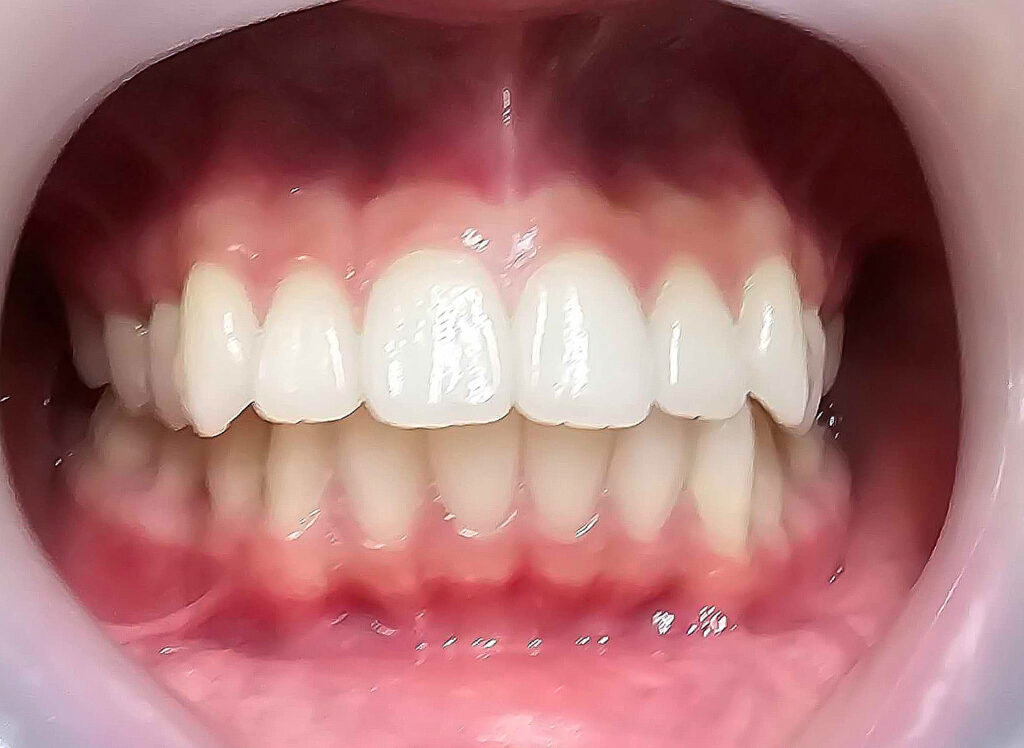

治療後

13歳頃、永久歯列になったところで、1期治療終了。虫歯のコントロール、歯磨き指導も十分に行ったため、虫歯や歯肉炎の発生もなく理想的な状態で完了できたと思います。あとは、高校1~2年生くらいに下顎の埋伏親知らずを抜歯して、通えれば20歳くらいまで半年メンテナンスが良いかもしれません。本当に口腔内の良好維持を考えている歯科医は、矯正で一時的に治った状態に満足しません。後戻りも考慮して、適齢期の親知らずの抜歯を行ったり、習癖の改善に取り組むでしょう。さらに患者さんが通院可能であれば、予後も追い続ける傾向があるでしょう。

下顎前歯叢生予防のため、高校1年になり、左右下埋伏の親知らずの抜歯を行いました。本人歯並びが良くなって、ホワイトニングも希望されましたので、行うことになりました。かなり白くなりました。個人的にこれが本当の人工物に頼らない理想的な治療方法(矯正+ホワイトニング)だと思ってます。これをもって、私の治療責任は果たされ、治療終了となります。恐らくこの子は、今のままの予防概念であれば、今後歯のトラブルに遭遇する確率は低いと考えられます。